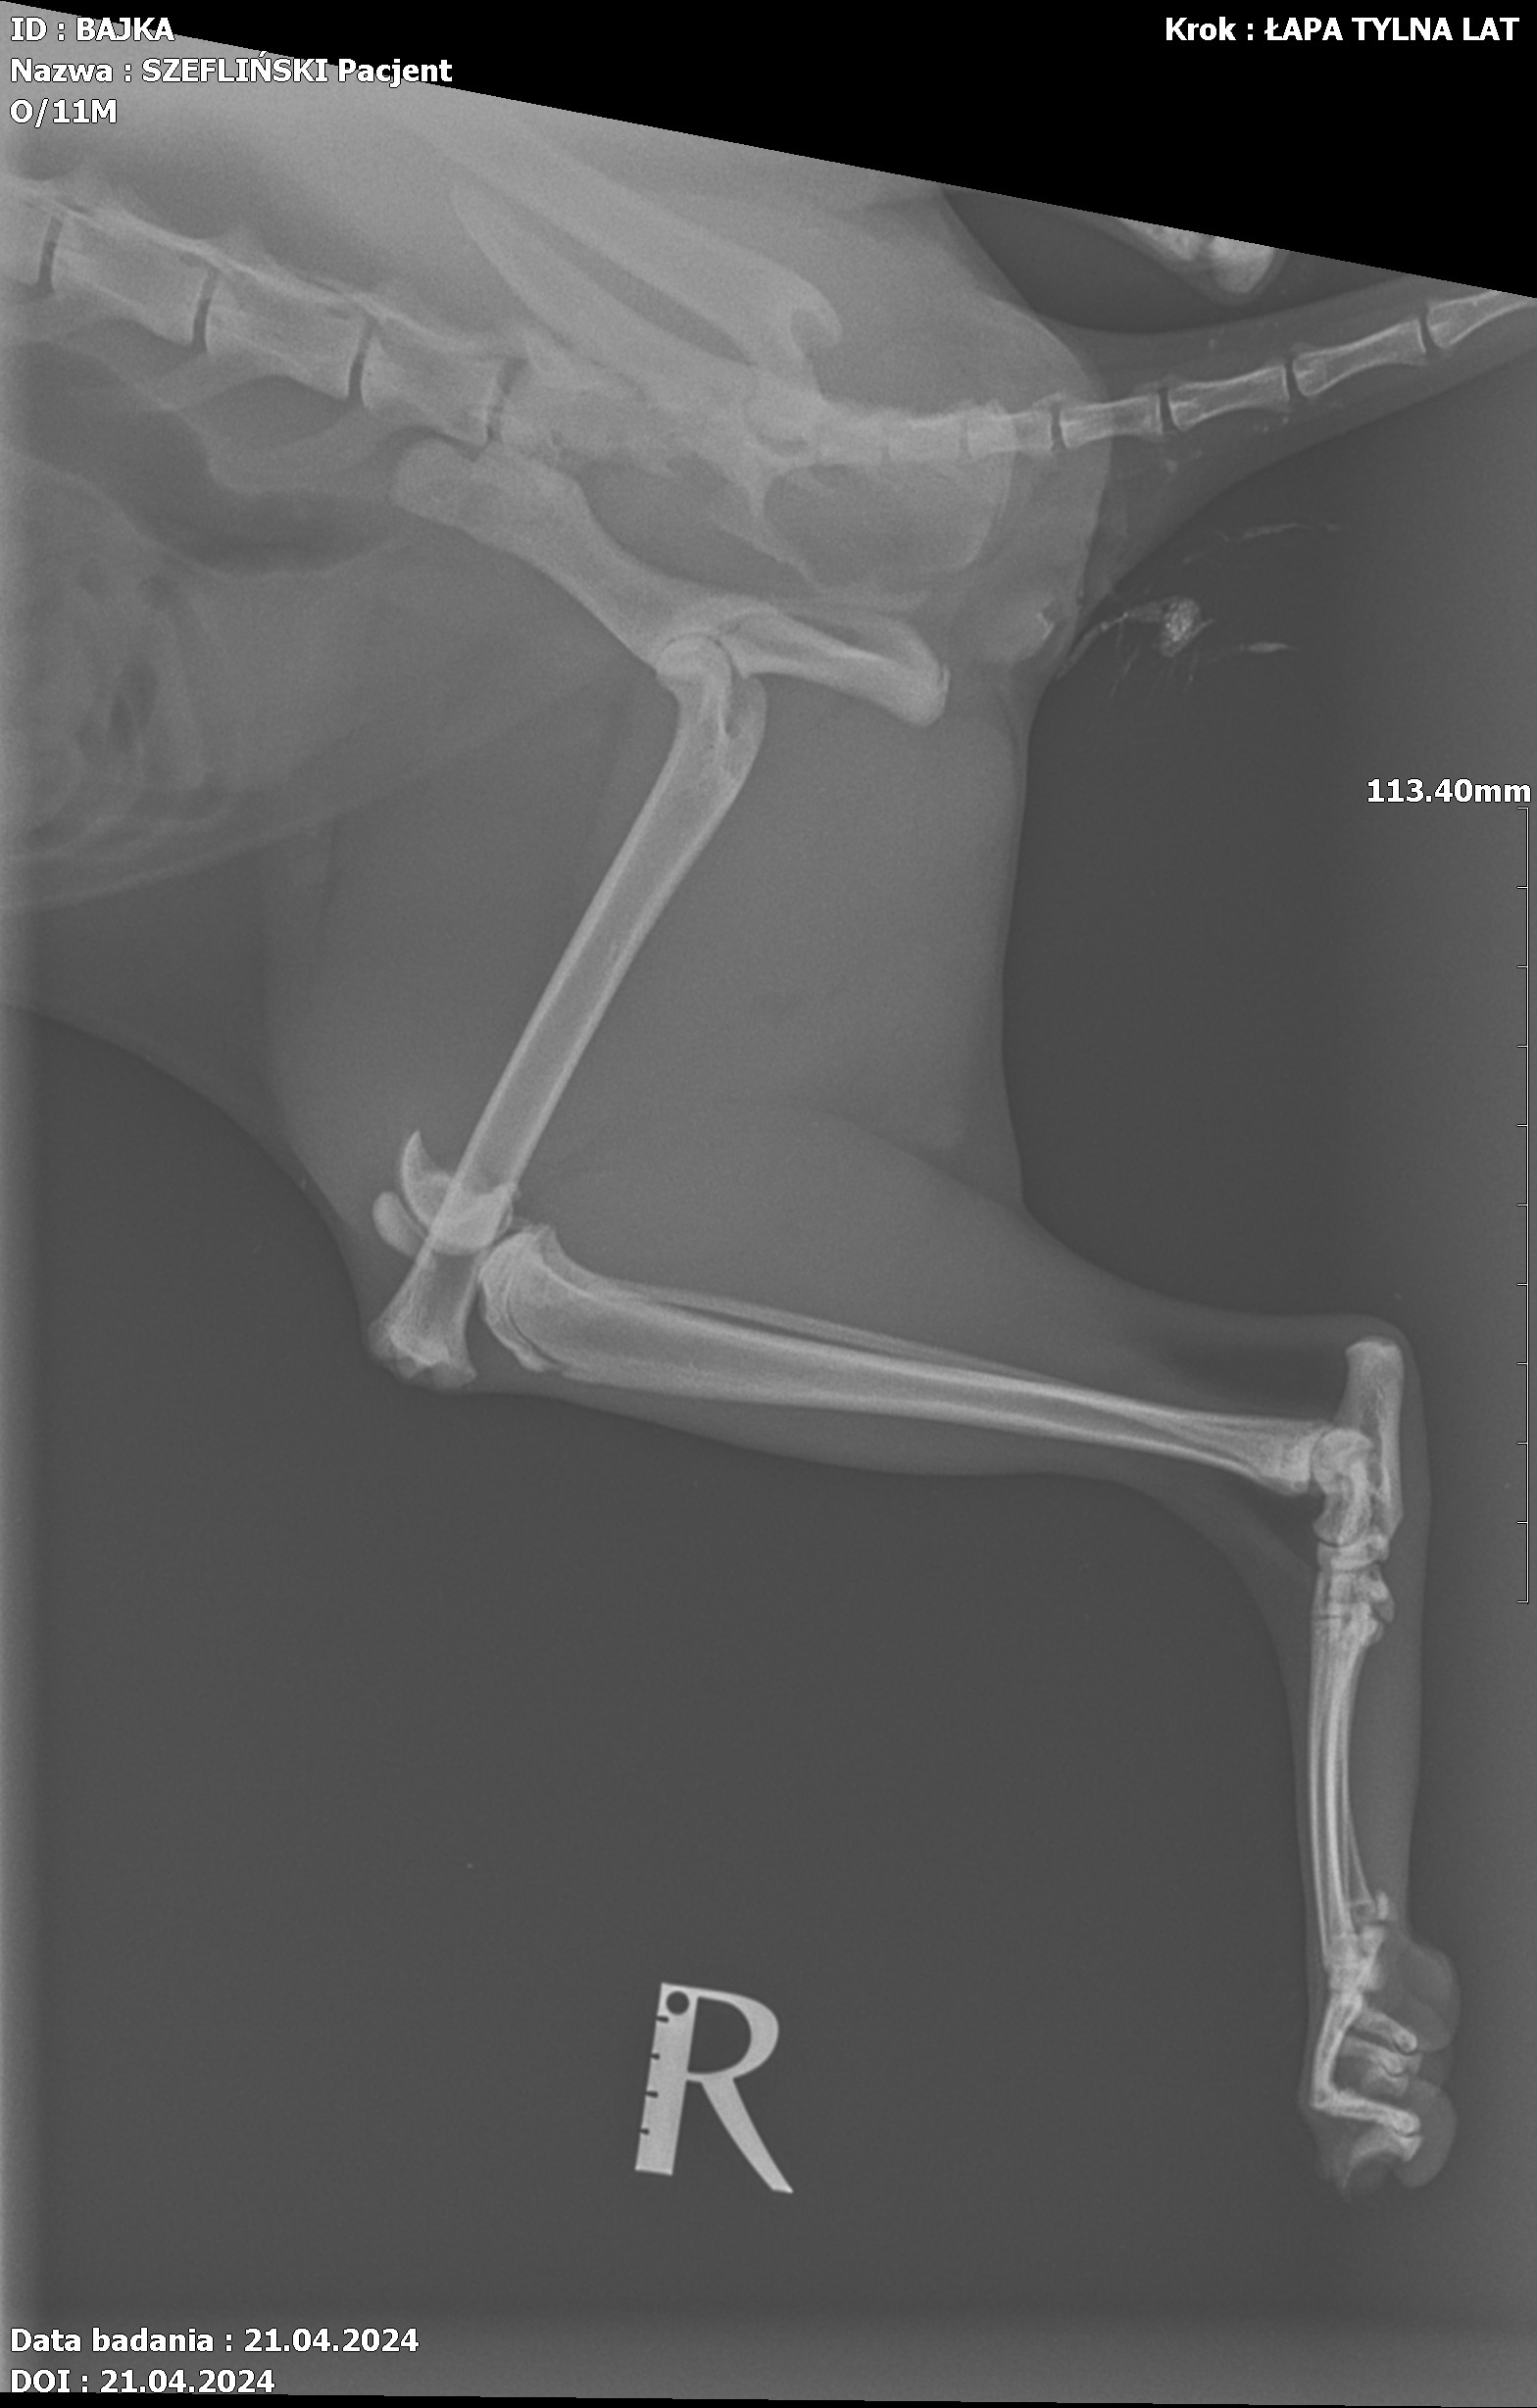

Jest szansa na uratowanie Bajki, ma złamaną prawą tylną łapką i pogruchotaną w kilku miejscach miednicę. Niestety - nasze możliwości finansowe się wyczerpały, życie dość mocno sie ze mną obeszło w ostatnich latach i nie mam generalnie nic. Dziś wydaliśmy wszystkie skromne oszczędności, żeby opłacić leczenie Bajki do tej pory.

Kochani, dzięki Waszym wielkim sercom Bajka dziś pomyślnie przeszła operację - DZIĘKUJEMY ????♥️???? Wielkie brawa dla lekarzy z lecznicy Cztery Łapy w Jeleniej Górze ! Koszt operacji wyniósł 3260 PLN plus każdorazowa wizyta kontrolna 30 PLN plus koszty dodatkowe za miesiąc, tj. wyjęcie śrub, leki, rehabilitacja. Dziś zapłaciłem 3000 PLN, załączam rachunek. Następne załączę przy kolejnych opłatach. Bajka wysyła miaubuźki (. ❛ ᴗ ❛.)